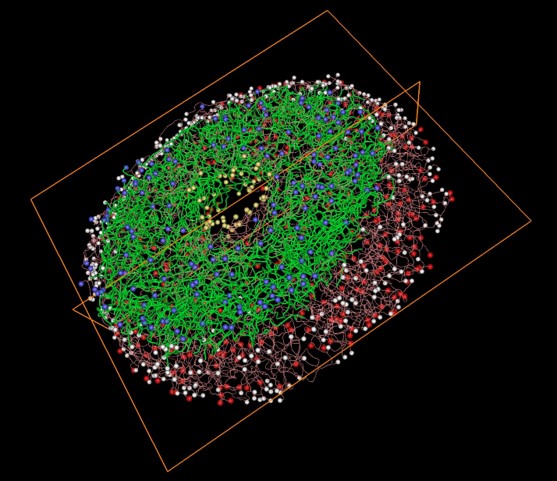

• A workflow for 3D reconstruction and quantification of the monkey optic nerve head vascular network

• PY Lee, Y Hua, BL Brazile, B Yang, L Wang, IA Sigal

• ASME Journal of Biomechanical Engineering,

image

• ASME Journal of Biomechanical Engineering